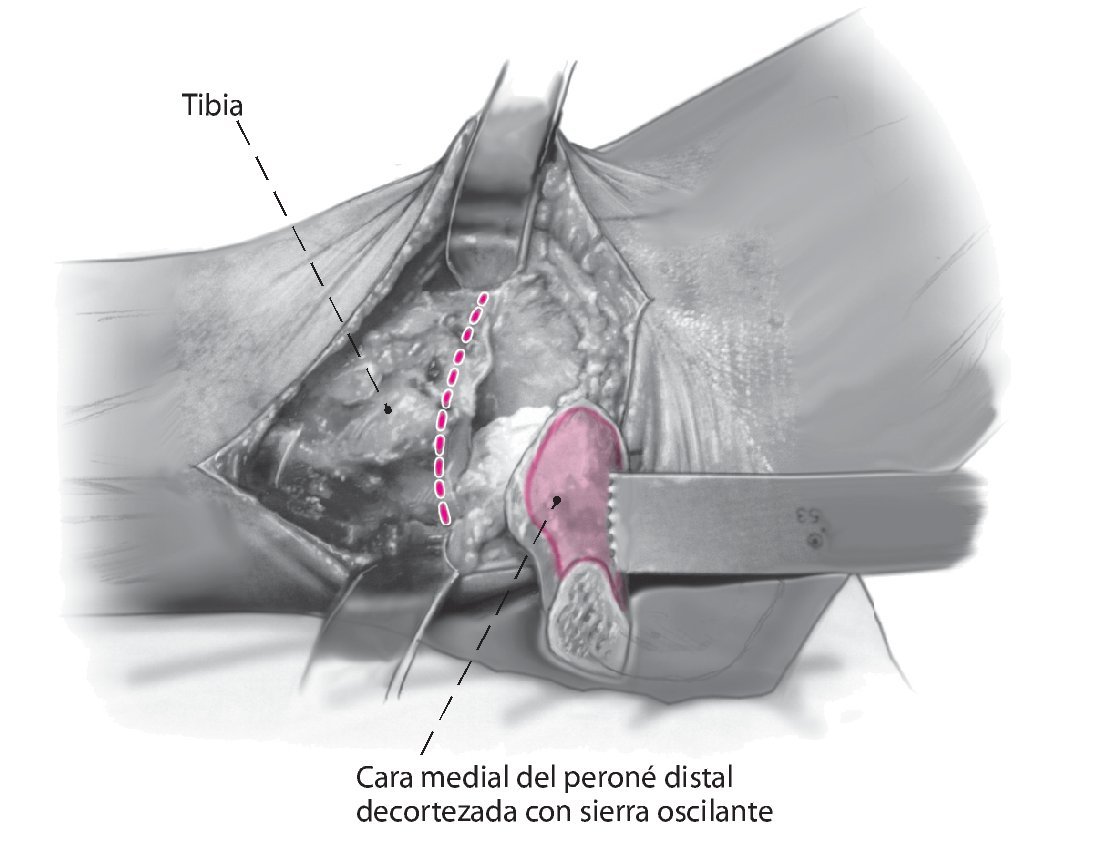

Fig. 5 Decortización de la cara medial del peroné distal con sierra oscilante. Esto aumenta la potencia biológica de la refijación.

Fig. 6 Realice la osteotomía en la tibial distal perpendicular al eje tibial. Cuando se realiza de medial a lateral, el paquete neurovascular posteromedial es visible y se puede supervisar. La resección de la tibia debe ser lo menor posible para evitar el acortamiento de la extremidad.